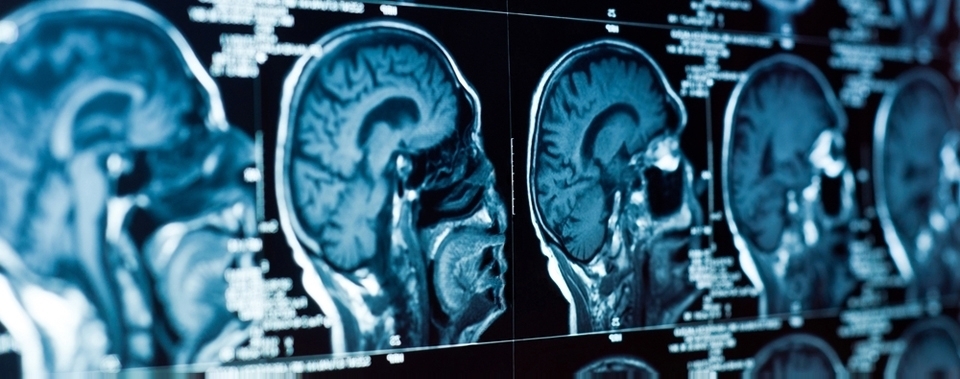

Die moderne bildgebende Technik ist ein wichtiger Teil des medizinischen Alltags. Unsere Kontrastmittel verbessern dabei die Darstellung von Strukturen und Funktionen des Körpers und werden beim Röntgen, bei der Computer- (CT) und Magnetresonanztomografie(MRT) sowie bei Ultraschalluntersuchungen eingesetzt.

Die moderne bildgebende Technik ist ein wichtiger Teil des medizinischen Alltags. Unsere Kontrastmittel verbessern dabei die Darstellung von Strukturen und Funktionen des Körpers und werden beim Röntgen, bei der Computer- (CT) und Magnetresonanztomografie(MRT) sowie bei Ultraschalluntersuchungen eingesetzt.